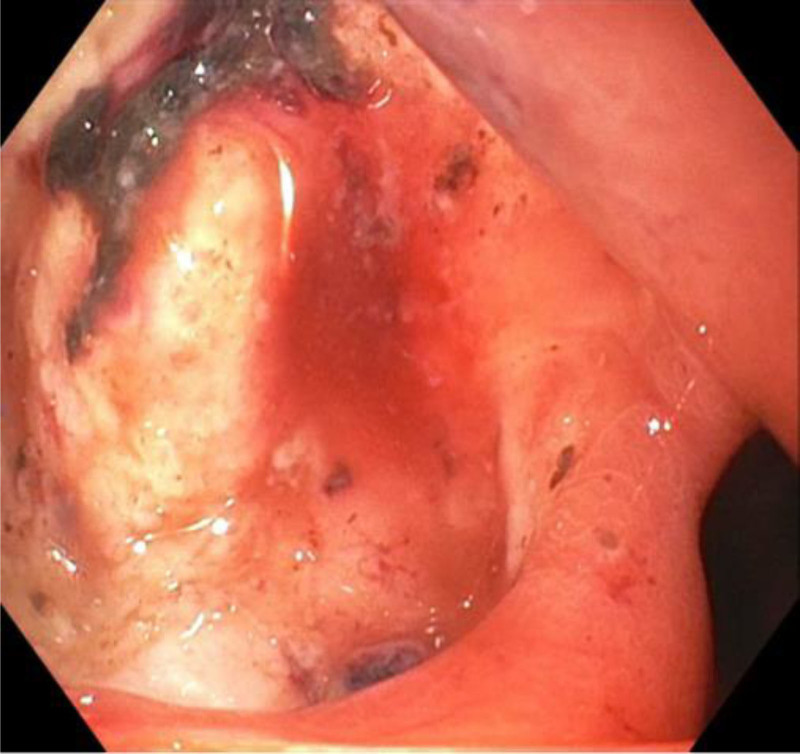

儿童幽门螺杆菌感染只占疾病的一小部分,而在发达国家,这一比例正在下降。典型的表现在文献中有很好的描述。我们报告了一位15岁的男性,他表现为黄疸、贫血、尿色深和腹痛,并被发现有幽门螺旋杆菌感染引起的十二指肠溃疡继发梗阻性黄疸。梗阻性黄疸是很少报道的十二指肠溃疡并发症,特别是在儿童。本报告回顾幽门螺杆菌感染,概述消化性溃疡疾病的并发症,并说明梗阻性黄疸作为儿童十二指肠溃疡的罕见表现。

Pediatric Helicobacter pylori infection represents a small proportion of disease that is otherwise decreasing in the developed world. Typical presentations have been well-described in the literature. We report a 15-year-old male who presented with jaundice, anemia, dark urine, and poorly characterized abdominal pain and was found to have obstructive jaundice secondary to a duodenal ulcer resulting from H. pylori infection. Obstructive jaundice is a seldom reported complication of duodenal ulcer, particularly in children. This report reviews H. pylori infection, outlines complications of peptic ulcer disease, and illustrates the rarity of obstructive jaundice as a presenting sign of duodenal ulcer in children.